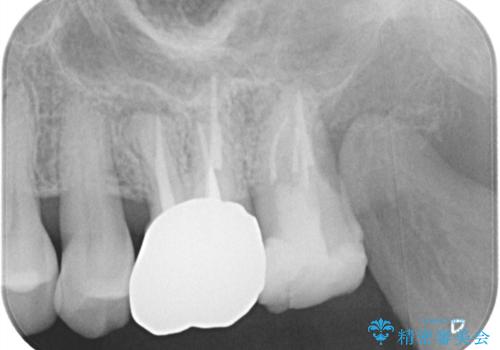

【根管治療】ズーンと痛い歯の治療。

- 奥歯付近がジーンと痛いことを主訴に来院されました。

左上7番の歯は、歯髄検査にて反応を示し、歯周ポケットはありませんでした。

親知らず抜歯を行い、痛みの変化や歯根吸収の有無を確認したのち、抜髄処置を行っています。

症状改善し、遠心の骨の回復も認めます。

バイオセラミックシーラーを使用して根管充填を行っています。